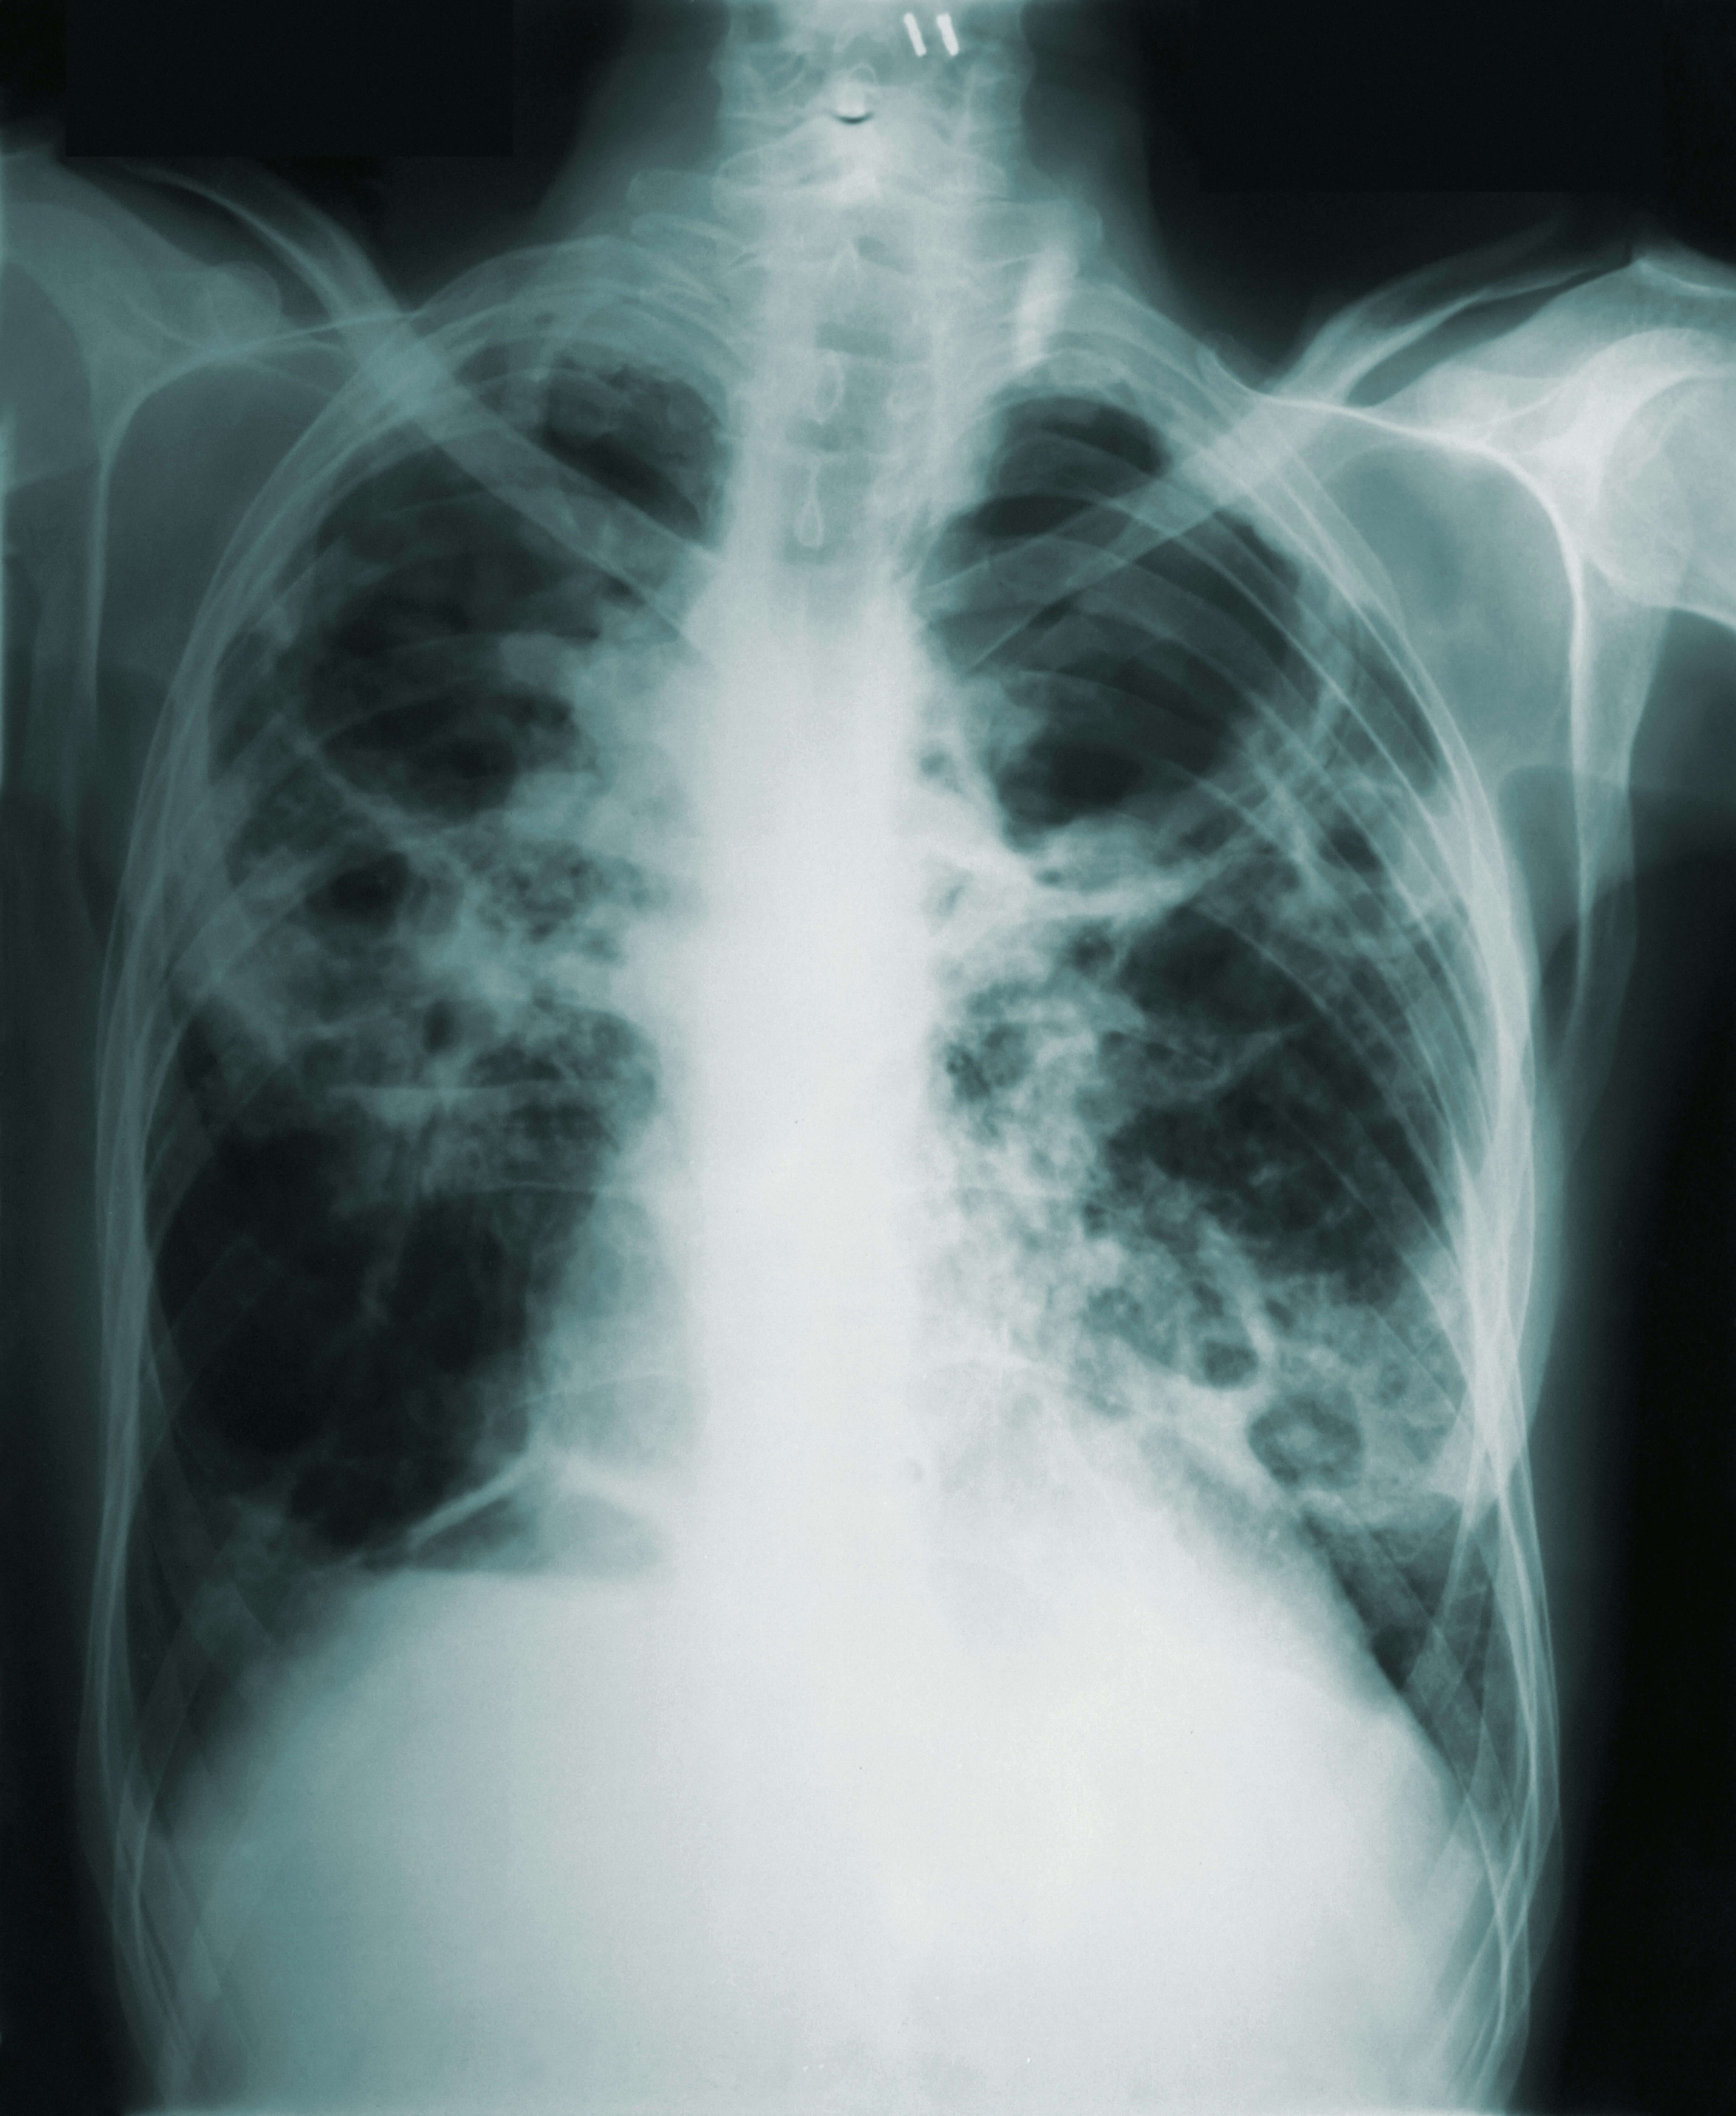

9. 잦은 감기와 폐렴이 발생함 🤒

한 번 감기에 걸리면 쉽게 낫지 않고, 폐렴이 자주 재발한다면 폐 내부에 종양이 존재할 가능성이 있습니다.

폐암은 기관지와 폐 조직에 영향을 주기 때문에 감기나 폐렴에 자주 걸릴 수 있습니다.

특히 기침과 가래가 지속적으로 남아 있는 경우 폐 건강을 의심해볼 필요가 있습니다.

반복적인 감기나 폐렴 증상이 있다면 단순 감기로 넘기지 말고 폐암 검사를 받아보는 것이 중요합니다.